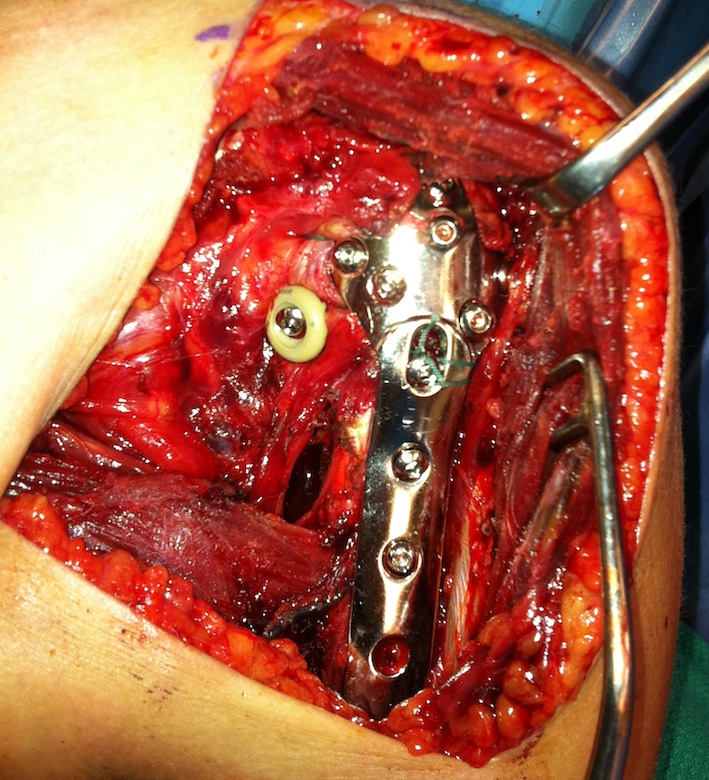

Beach chair / deltopectoral approach

- extensile approach - release CA ligament / release proximal pectoralis major

- can release anterior deltoid insertion from lateral clavicle if needed (intra-osseous repair later)

- protect musculocutaneous nerve under conjoint, minimal retraction

- protect the axillary nerve on inferior border of SSC medially

- identify and release biceps tendon

Reduction

- identify and tag greater and lessor tuberosities with Mason Allen sutures

- reduce head onto shaft (head is displaced posteriorly) and avoid varus

- +/- fibular strut allograft

- provisionally fix with 2 mm k wires

Apply plate

- lateral to biceps with single cortical screw in oblique hole